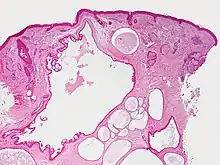

Hidrocystoma (also known as cystadenoma,[1] a Moll's gland cyst,[1] and a sudoriferous cyst[1]) is an adenoma of the sweat glands.[2]: 787

Hidrocystomas are cysts of sweat ducts, usually on the eyelids.[3]: 664 They are not tumours (a similar-sounding lesion called hidroadenoma is a benign tumour).

Hidrocystomas usually arise from apocrine glands. They are also called cysts of Moll or sudoriferous cysts. A type of hidroadenoma that arises from eccrine glands is uncommon.